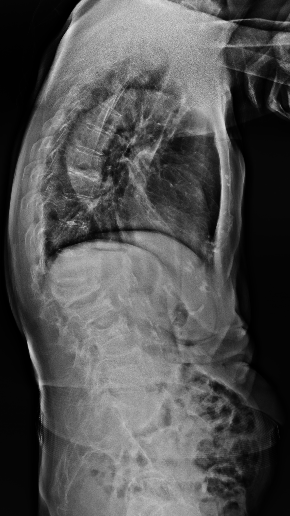

胸腰椎MRI检查结果显示:腰1椎体新近压缩性骨折伴积气,继发椎管狭窄;腰2、3椎体及腰4椎体上缘新近骨折。

影像学结果明确了患者为“骨质疏松伴多节段病理性骨折”,并伴有明显的脊柱后凸畸形和腰椎不稳。骨密度检测T值-4.25,提示重度骨质疏松。

影像学检查提示多节段脊柱病变

接诊后,科室为吴婆婆安排了详细的影像学检查,结果令人震惊。磁共振显示,她的骨折远非此前所知的一处,骨折下方的三节椎体腰2至腰4多个椎体都出现了新鲜压缩性骨折。更关键的是,最初的腰1椎体骨折并未愈合,属于“骨折不愈合”状态,并在重力作用下逐渐塌陷,导致脊柱后凸畸形(俗称“驼背”)。

术前(左)和术后(右)对比: 术后脊柱后凸矫正,骨折椎体强化固定